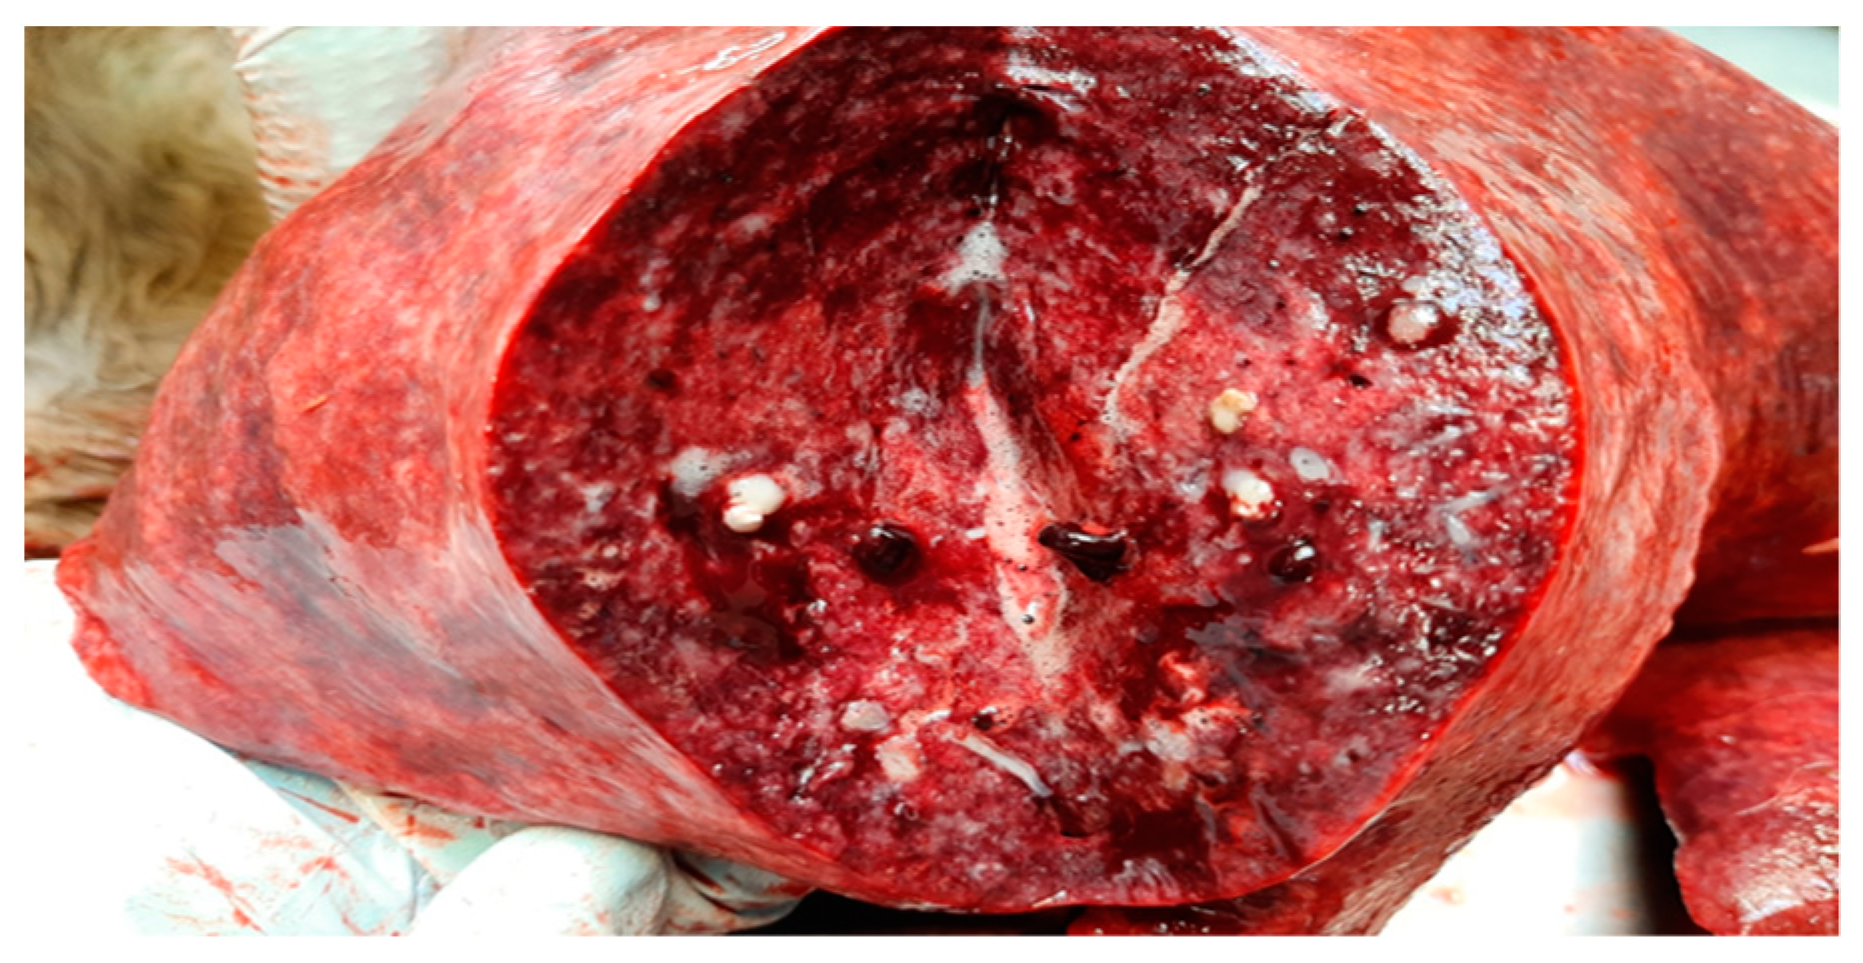

2.1. Necropsy